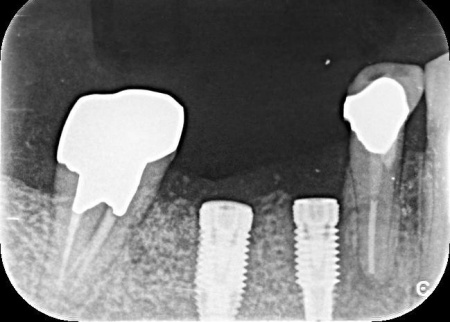

インプラント体と骨の結合を確認しました。